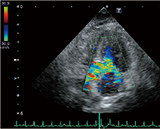

特集●部位別の基本描出シリーズ 循環器編③ 心臓 後天性疾患 「超音波検査」(動画1~5)

特集●部位別の基本描出シリーズ 循環器編③ 心臓 後天性疾患 「超音波検査」(動画6~12)

特集●部位別の基本描出シリーズ 循環器編③ 心臓 後天性疾患 「超音波検査」(動画13~16)

特集●部位別の基本描出シリーズ 循環器編③ 心臓 後天性疾患 「超音波検査」(動画17~24)